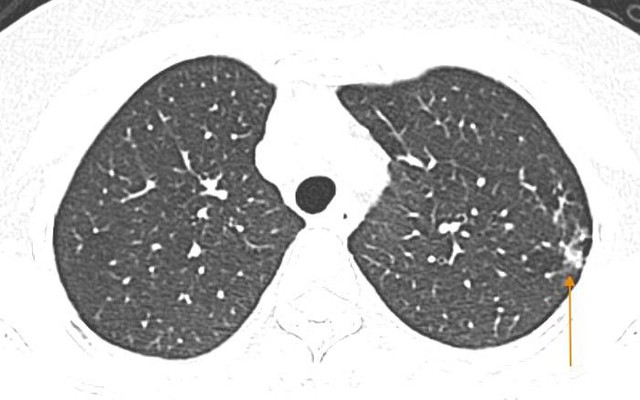

Mắc cúm A, người phụ nữ Hà Nội phổi như bị bóp nghẹt, "không thể thở nổi"

Sống khỏe 2025-02-08T16:08:00Thấy người mệt mỏi, gai người và sốt, người phụ nữ tự mua thuốc về điều trị. Tuy nhiên, ngay trong đêm, chị đã phải vào viện khám do khó thở.